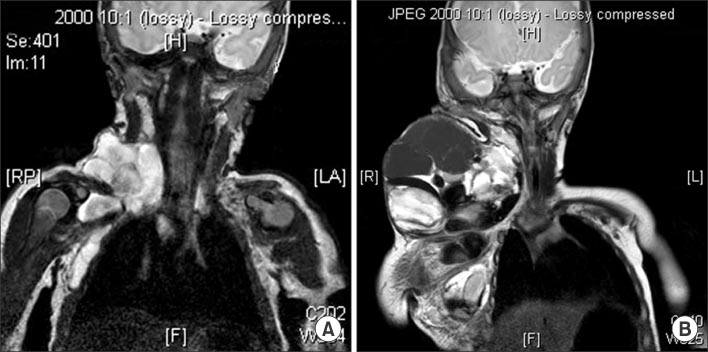

(A) MRI shows macrocystic lymphatic malformations which are involving from right neck to axilla before OK-432 sclerotherapy (patient No. 9). (B) Intralesional hemorrhage happened one month after sclerotherapy.

jkaps-21-17-g004.jpg